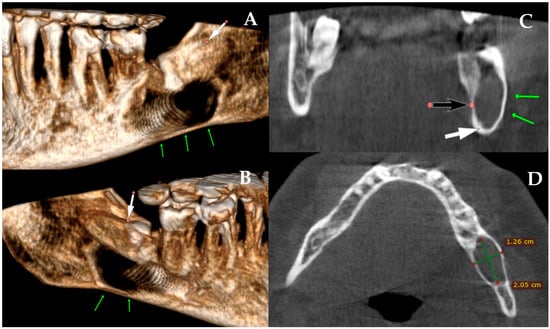

Figure 2. The role of CBCT in contemporary dentistry and oral and maxillofacial surgery remains highly important. Many worrisome or insufficiently diagnosed bone lesions, as well as the extent of bone loss and the risk of fracture, can be more accurately identified and evaluated using CBCT. In the first case presented in Figure 1, a CBCT revealed a well-circumscribed, unilocular, pericoronal radiolucent lesion in the left posterior mandible, enveloping the crown of the impacted mandibular third molar ((A) white arrow (decreased bone volume) shows the impacted third molar). The lesion extended anteroposteriorly from the mesial root of the second molar to the anterior aspect of the mandibular ramus (B). CBCT demonstrated significant buccolingual expansion with diffuse thinning of both buccal and lingual cortical plates ((AC) green arrows showing thinning along the inferior mandibular border), although no cortical perforation was detected. The inferior alveolar canal was displaced inferiorly and slightly lingually ((C) white arrow: IAN position; black arrow: lingual plate thinning), but its corticated borders remained intact. The lesion’s internal architecture was homogeneous, without septations or calcifications. The impaction was classified as complete bony impaction, with the cystic lumen closely surrounding the enamel–cementum junction (B) (red dots point the arrow). Mild displacement but no resorption of the adjacent second molar roots was observed. The inferior border of the mandible remained continuous, with no radiographic signs suggestive of pathological fracture risk. The axial view additionally demonstrated the degree of buccolingual expansion with dimensional measurements (D). Based on CBCT findings, surgery was performed under local anesthesia. A conservative mucoperiosteal flap was elevated to expose the cyst cavity. The lesion was accessed, and complete enucleation with curettage of the cyst lining was carried out. Minimal bone removal was performed to expose the crown of the impacted mandibular third molar and facilitate tooth extraction. After irrigation, the flap was repositioned and sutured primarily. The endodontically failed mandibular left first molar (tooth #36) was also extracted in the same procedure. Although PMP or temporary intermaxillary fixation (IMF) could have been considered, particularly given the degree of buccolingual expansion, both were deferred because intraoperative stability was satisfactory, cortical continuity was maintained, and no crack propagation or bone bending was palpated. Nevertheless, this case demonstrates that even when the mandible appears stable during surgery, marked cortical thinning on CBCT can still increase the likelihood of a delayed postoperative fracture. For this reason, such findings should prompt careful postoperative follow-up or consideration of preventive fixation [5]. In this case, an immediate PMP with a plate or a plate with a bone graft could be used; however, the decision to perform PMP is highly patient-specific and dependent on numerous individual factors.